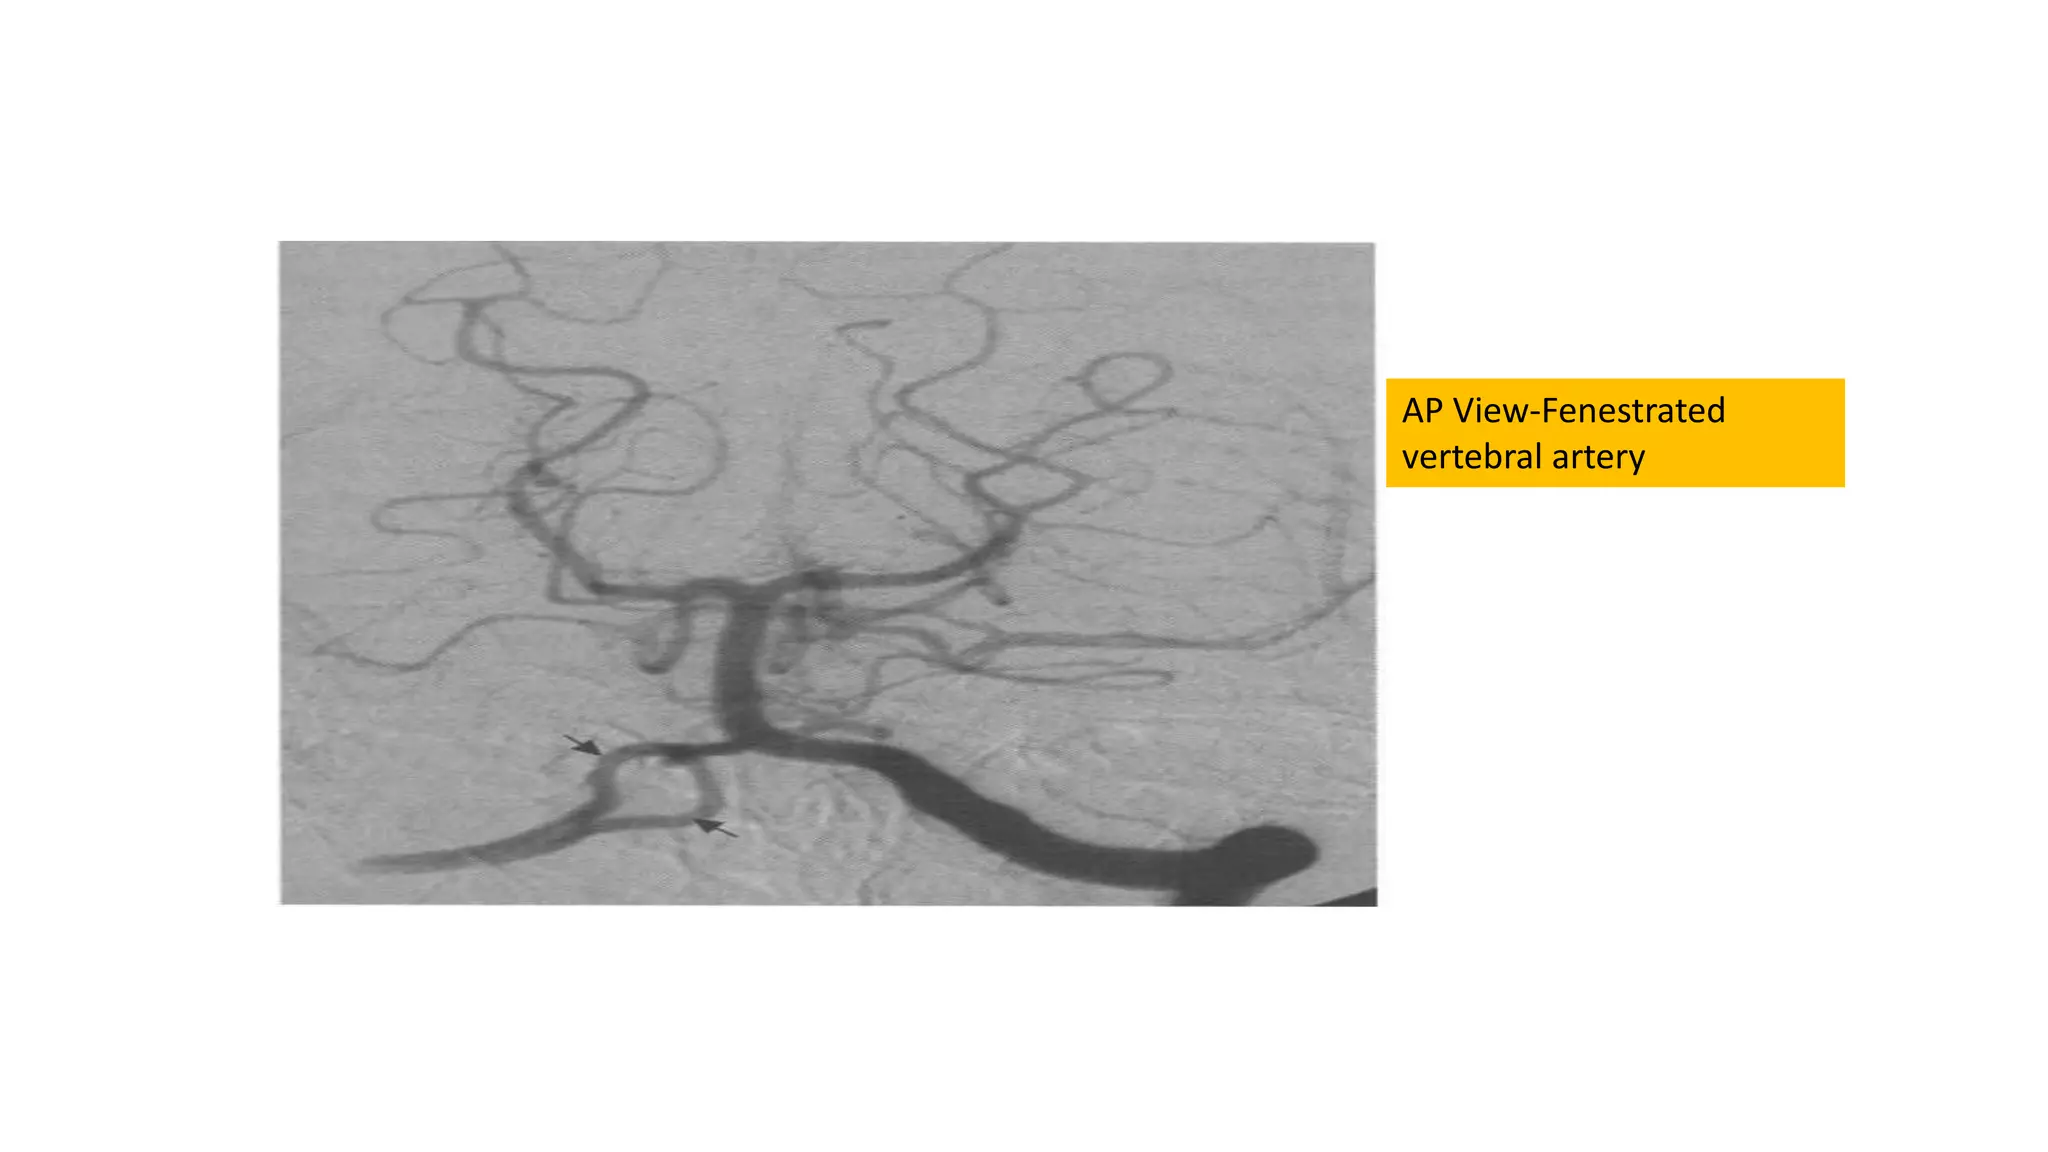

Fenestration and duplication

AP View-Fenestrated

vertebral artery